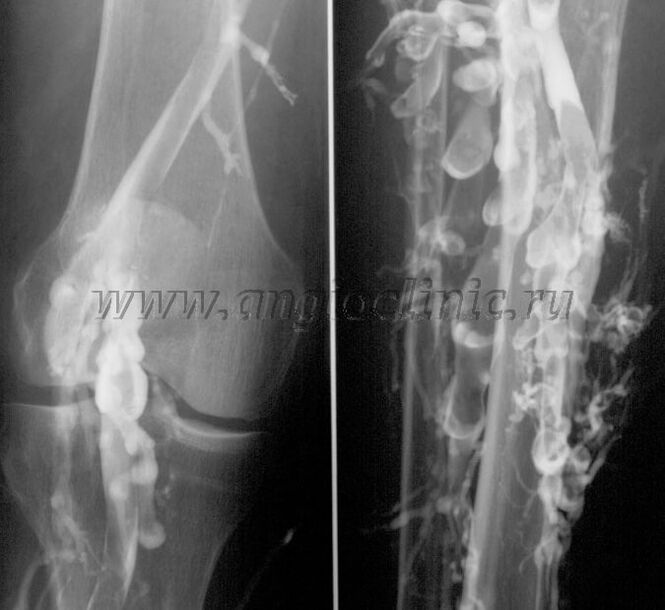

Контрастна венографија

Обично, ултразвучното скенирање е доволно за целосна дијагноза на венската патологија, но во некои случаи е неопходно да се проучи односот помеѓу состојбата на длабокиот и површинскиот венски систем, особено во случај на релапси на проширени вени и секундарни проширени вени.

За да се решат овие проблеми, се користи рендгенско испитување со контраст. Сафенозните вени се пробиваат и се администрира контраст. Движењето на контрастот се забележува на мониторот на рендген апаратот и се вршат сите потребни тестови и проекции. Во моментов, венографијата за проширени вени се користи многу ретко.